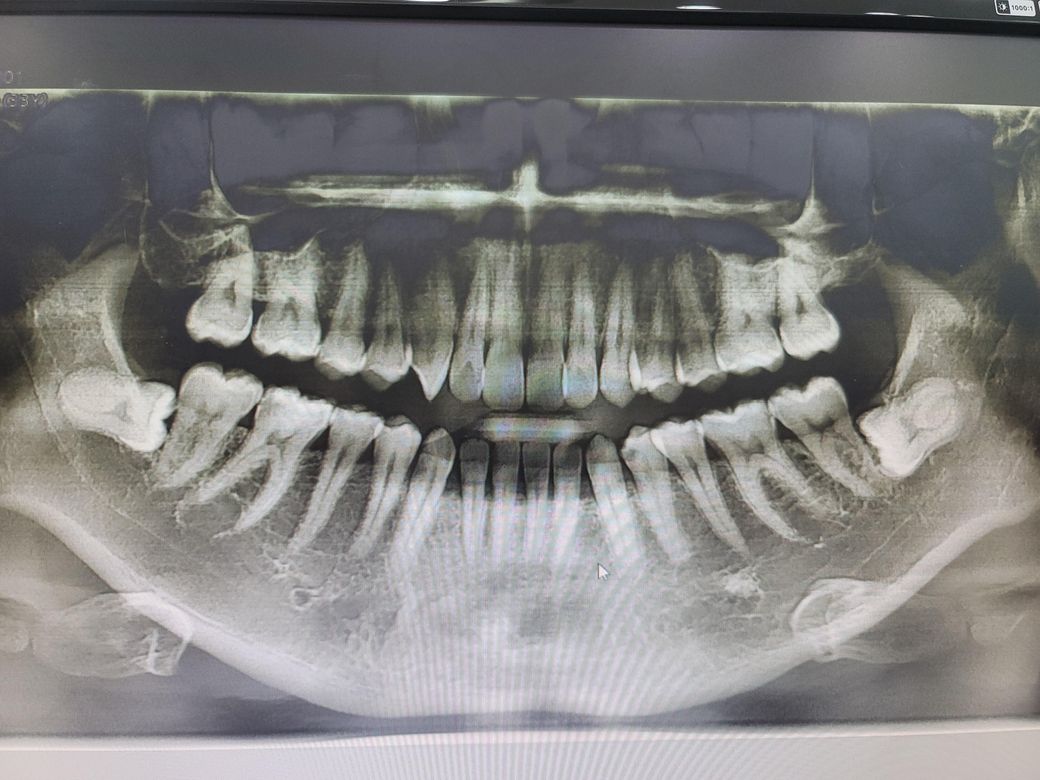

아래 사랑니가 안나와요..계속 유지하고있으면 될까요?

현재 34살입니다..위에 사랑니는 다 뺐는데 아직도 아래 사랑니가 나오지않고있습니다.

현재 아무런통증은 없습니다. 병원에서 끝에 어금니만 깨끗히 닦으라고 하시고 사랑니 나올 확률은 없고 굳이 뽑을필요도 없다고 하는데 계속 신경쓰이네요 ...

엑스레이 상에 치료해야할 충치가 얼마나 있는지 알수있나요?병원에서는 13개가 있다고 하는데..생각보다 너무 많은거 같아서요..선생님들의 도움이 필요합니다..

엑스레이상으로는 충치여부는 확인은 어렵습니다. 엑스레이상에 매복사랑니의 경우 앞 어금니에 걸리는 경우가 대부분입니다. 이런 경우 매복 사랑니를 그냥 두면 바로 앞 어금니를 상하게 하는 가능한 빨리 뽑는 것이 좋습니다. 지금 당장 통증 없다고 두면 바로 앞 어금니가 서서히 상하게 되어 40세 지나며 사랑니와 바로 앞 어금니와 같이 뽑는 경우가 생길 수 있습니다. 따라서 보다 큰 병원을 방문하여 검사를 받고 매복니 발치여부를 다시 한번 확인하길 권합니다.

사랑니는 이미 다 자란 형태로 잇몸 아래에 존재합니다. 물론 잇몸 아래에 있으므로 꼭 뽑지 않아도 되나 언젠가는 뽑아야 할 날이 올 수도 있어 보입니다. 충치는 단순히 현재 사진으로만 판단이 불가능합니다. 현재 사진은 3차원적인 사진을 2차원으로 바꾼 것이므로 상당히 왜곡이 되어 있고 구강 내 시진 검사와 함께 이뤄져야 정확한 진단을 할 수 있습니다.

사랑니 위치는 거의 변하지 않을것같습니다. 잇몸이 내려가서 사랑니가 약간 노출되면 모를까 치아가 맹출될 가능성은 없습니다. 사진상으로 큰 충치는 볼수 있지만 씹는면에 잇는 충치들은 확인하기가 어렵습니다.

파노라마 사진으로는 충치 판별을 해드리는 것이 힘들며 사랑니는 매복되어 있더라도 발치를 하시는 게 좋습니다